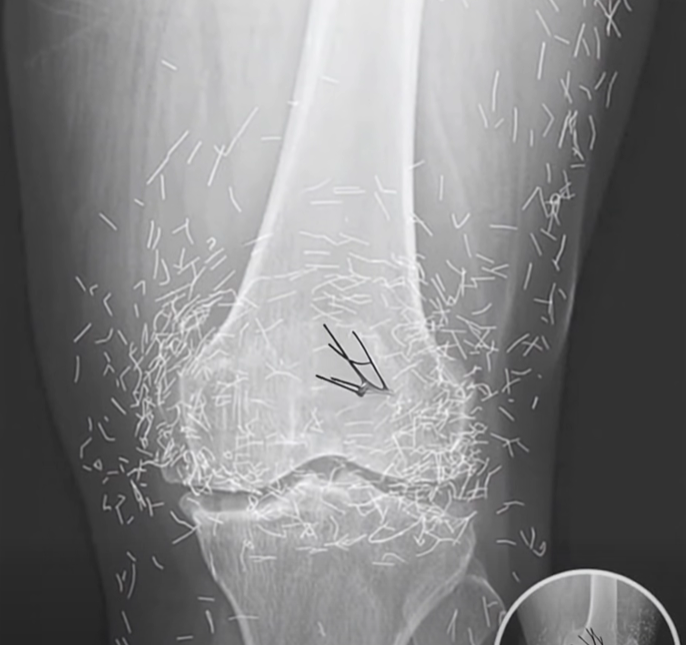

When a 65-year-old woman in South Korea went to the hospital for routine tests, she expected doctors to tell her what she already knew—that her painful, swollen knees were caused by arthritis. Instead, her X-ray revealed something no one could have predicted: her joints were filled with hundreds of tiny gold needles. The shocking discovery left doctors stunned and raised questions about a little-known treatment practice that had gone far beyond what most people would consider safe.

The woman had been struggling with osteoarthritis, a common but painful condition where the cartilage in joints wears down, causing stiffness and inflammation. Traditional treatments such as pain medication and anti-inflammatory drugs hadn’t worked for her, and the side effects were becoming unbearable. Desperate for relief, she turned to acupuncture, a centuries-old practice widely used across Asia. Unlike standard acupuncture sessions, however, this treatment involved leaving thin gold needles in her body permanently, with the belief that they would provide continuous pain relief.

But what might sound harmless in theory quickly raised red flags in the medical community. Experts warn that leaving metal objects inside the body carries serious risks. The immune system can attack the foreign material, leading to chronic inflammation or tissue damage. Infections are also a major concern, and the presence of metal can make diagnostic scans harder to interpret, complicating future medical care.

Perhaps the greatest danger comes if a patient with these implants ever needs an MRI. Because MRI machines use powerful magnetic forces, metal objects can shift or move inside the body, potentially puncturing blood vessels or damaging tissue. While acupuncture remains a respected and widely practiced therapy for pain management, doctors stress that extreme variations—like permanent gold needle implants—should be approached with caution. This woman’s case, published in the New England Journal of Medicine, is a reminder that even traditional remedies can carry unexpected risks when taken to unconventional extremes.